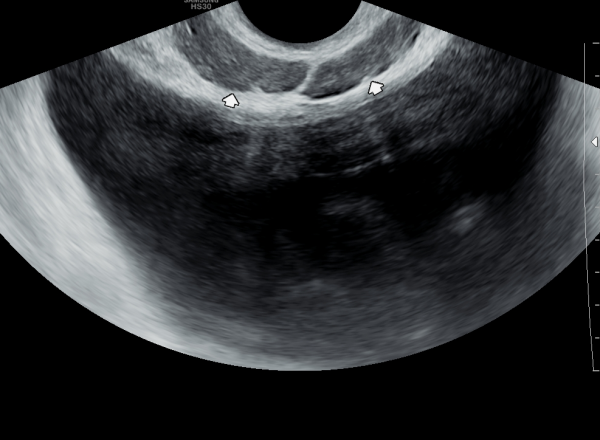

수년 전부터 배뇨중 타는 듯한 느낌의 작열 감과 배뇨 장애로 여러 비뇨기과에서 치료를 했으나 증상의 호전이 없어 내원 당일 검사한 경직장 전립선

초음파 검사 상 사정관 입구의 미세 결석과 사정관 낭종이 관찰되는 사진입니다.

A transrectal prostate ultrasound image taken on the day of the visit from a patient who had experienced a burning sensation during urination and voiding dysfunction for several years. Despite receiving treatment at multiple urology clinics, symptoms did not improve. The ultrasound shows microcalcifications and a cyst at the opening of the ejaculatory duct.